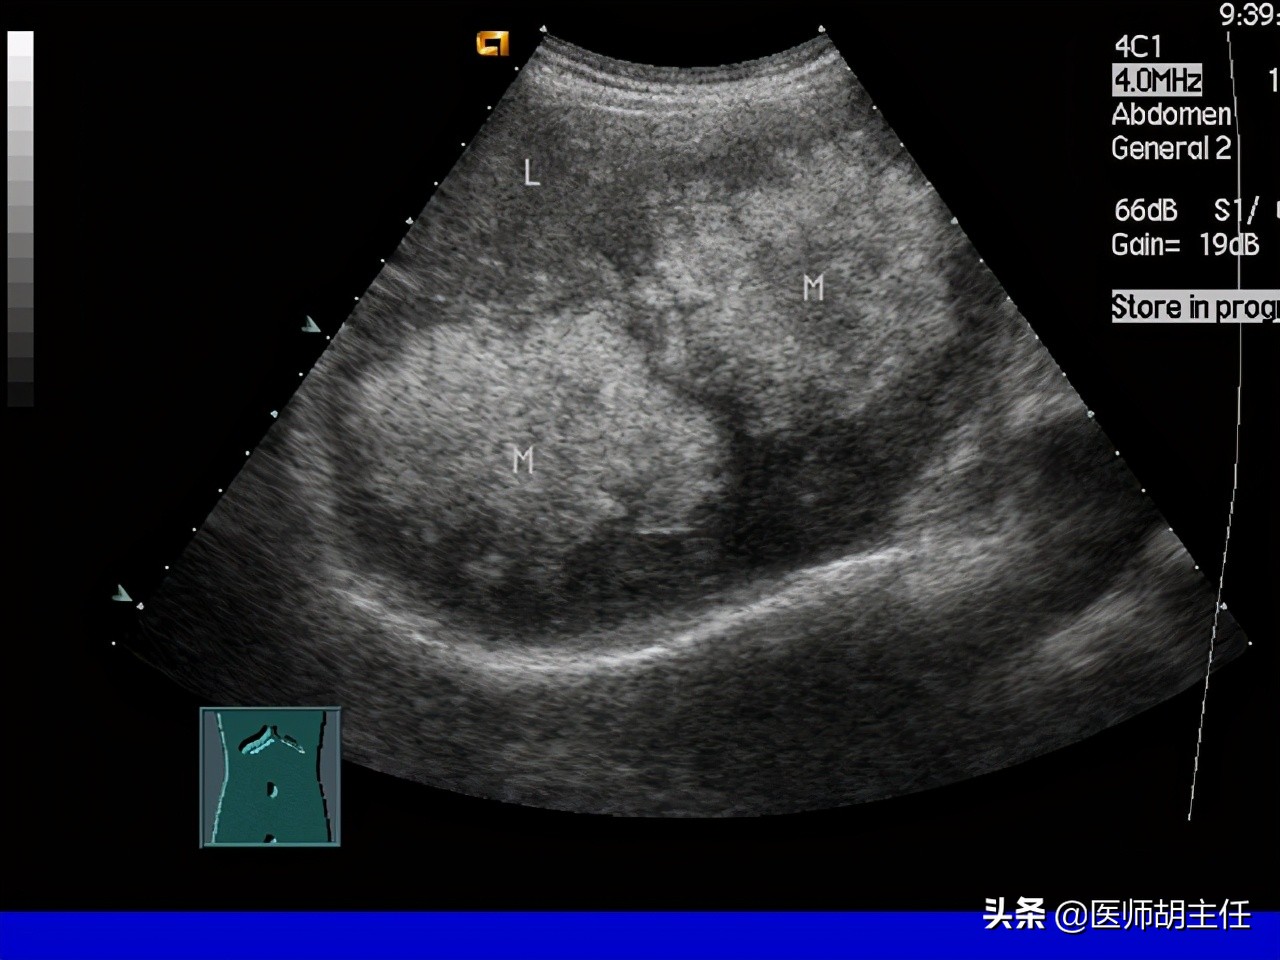

要想确诊肝癌,需要做很多检查,从不同方面得到数据来帮助鉴别判断,如实验室、影像学、肝穿活检等, 这当中超声是首选方法,借助它可以达到有效筛查肝癌的目的,操作方便、价格亲民加上无创性都是其优点,可以检出肝内直径>1cm的病灶, 如果再结合多普勒、超声造影剂就能判断病变的良恶性,且帮助阴道肝穿刺。